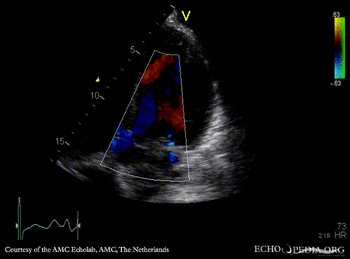

Severe aortic regurgitation

M-Mode through aortic valve PLAX: Color Doppler signal shows severe aortic regurgitation